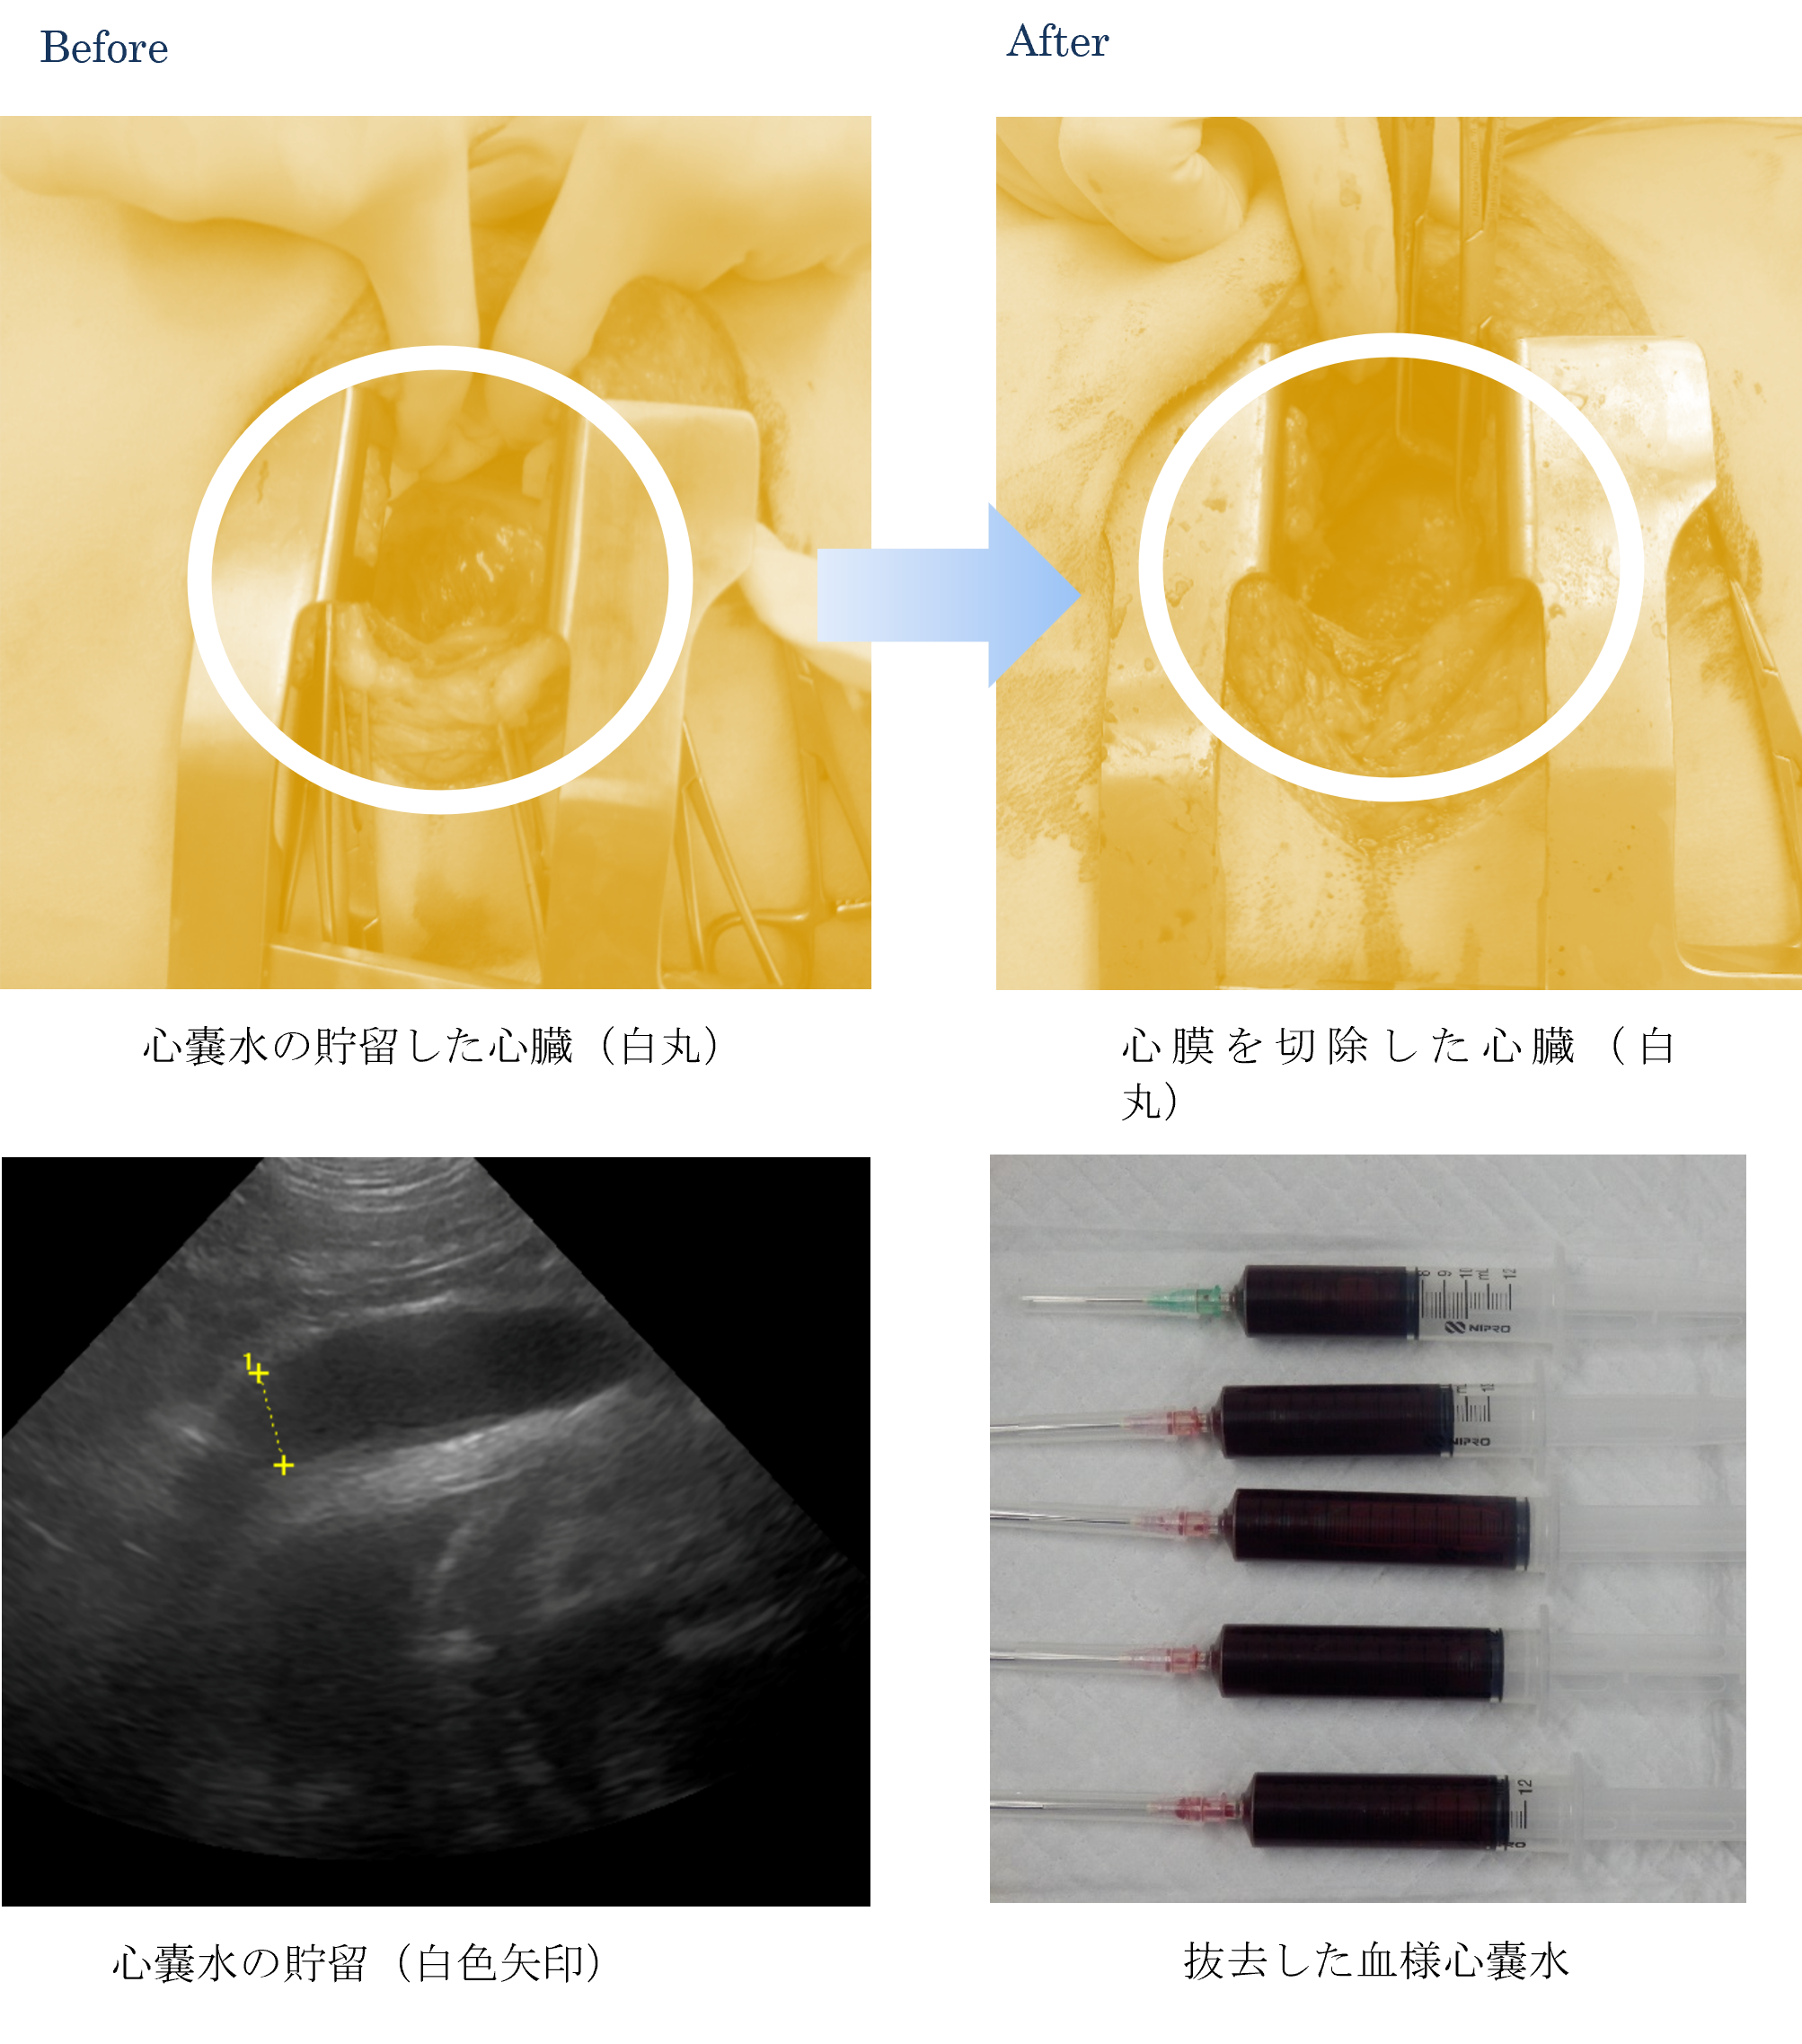

各種検査より、心タンポナーデによる循環不全と診断しました。

ご家族と相談した結果、緊急的に超音波ガイドによる心嚢水の抜去を行いました。

そのためご家族と相談した結果、心嚢膜(心臓の周りの膜)の切除の手術を行いました。

手術後の心嚢水は胸腔から吸収され、心嚢水の抜去は必要としなくなりました。